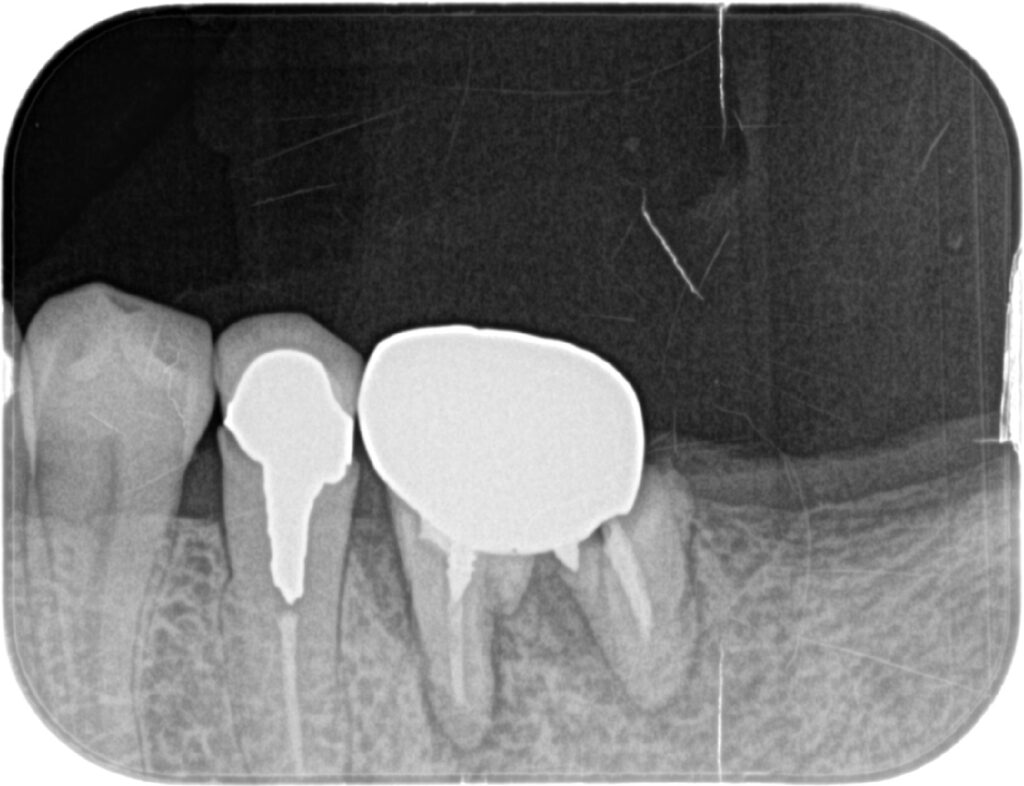

左下奥歯を2本インプラント治療した症例

| 主訴 | 前歯欠けた。その他虫歯治療してほしい。 |

| 年齢 | 70代女性 |

| 治療内容 | 根尖病巣で排膿もあり残すことが難しいため抜歯しインプラント治療へ。 歯槽骨の量が不足している場合に、人工骨や自家骨を移植し、特殊な膜で覆うことで骨の再生を促し、インプラントを埋入できるようにするGBRという治療法も併用。 最終的なかぶせものはご自身の歯と変わらないような仕上がりとなっています。 |

| 抜歯部位 | 左下6 |